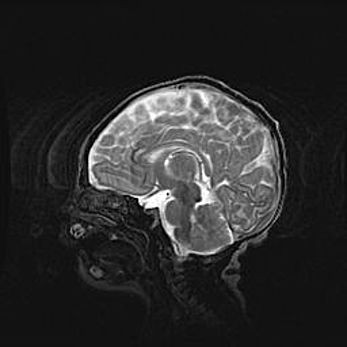

Церебральная ишемия II.

Возраст: 5 дней

Вес: 3400 г

Пол: женский

Окружность головы: 35 см

Срок гестации: 39 недель

Церебральная ишемия – это заболевание, характеризующееся недостаточностью (гипоксией) либо полным прекращением (аноксией) снабжения мозга кислородом по причине закупорки одного или нескольких сосудов. Это приводит к  что метаболическим расстройствам различной степени тяжести в тканях головного мозга, развитию коагуляционных некрозов и гибели нейронов.